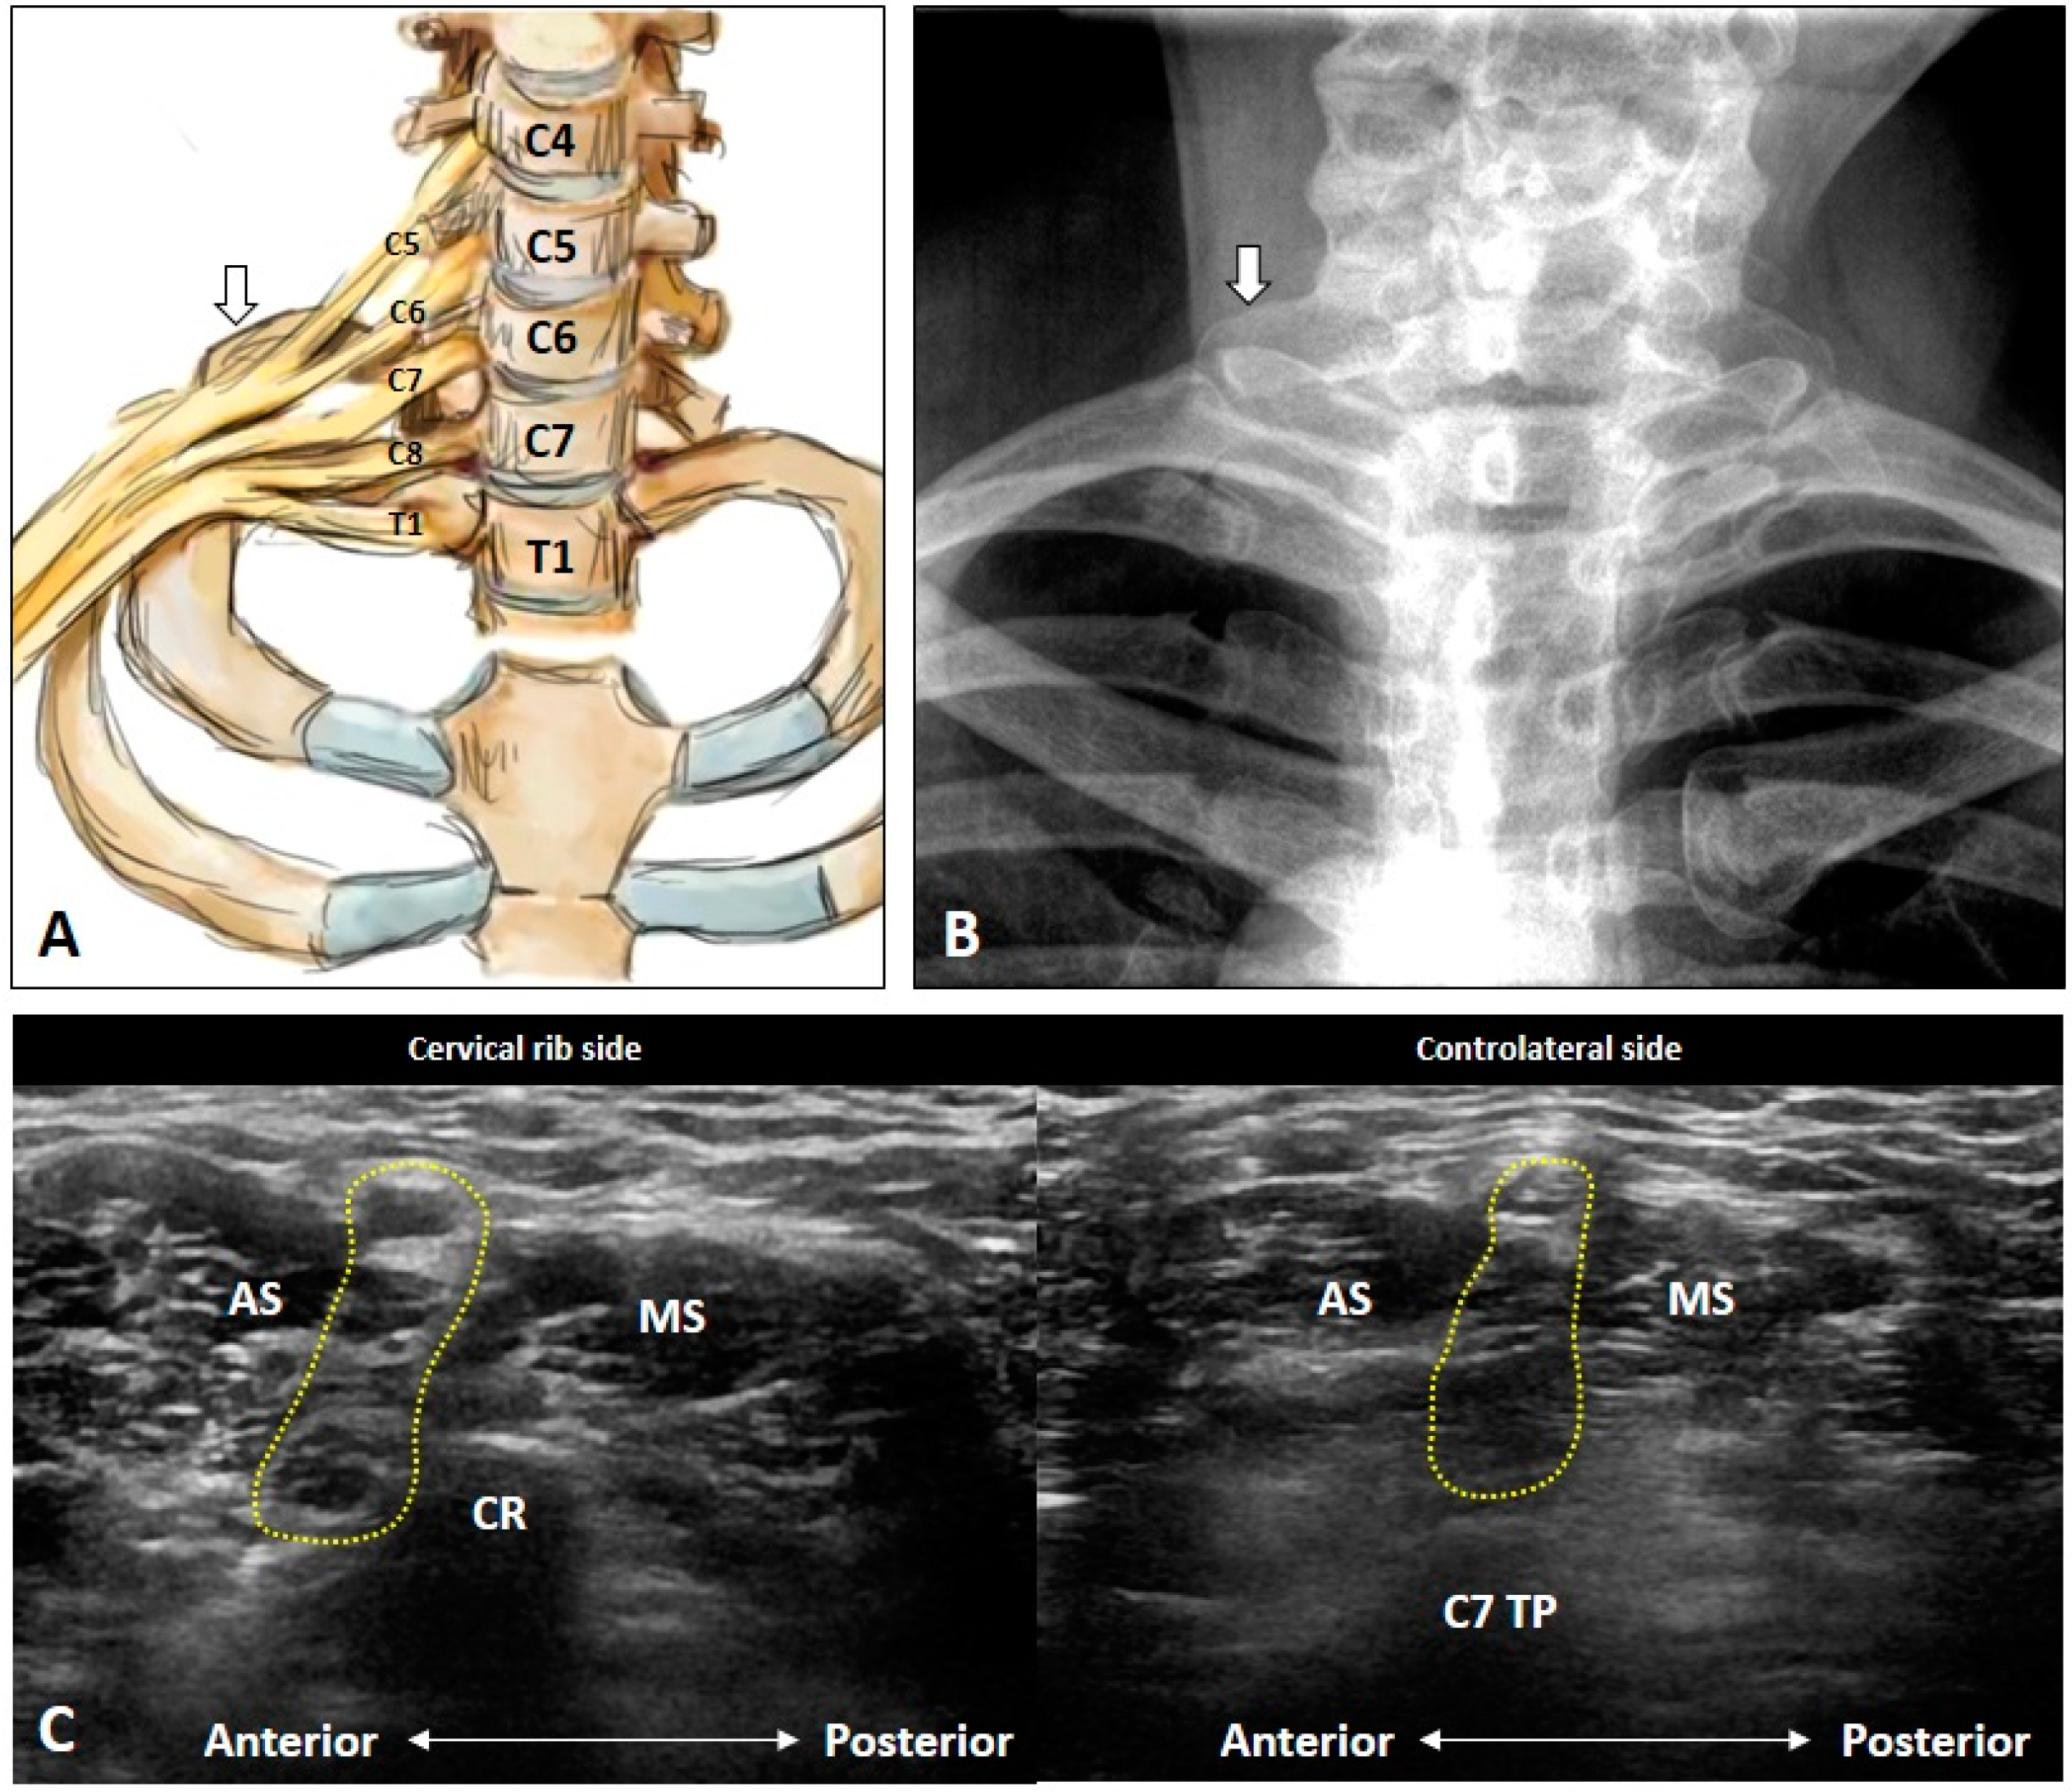

4.5. Thoracic Outlet Syndrome